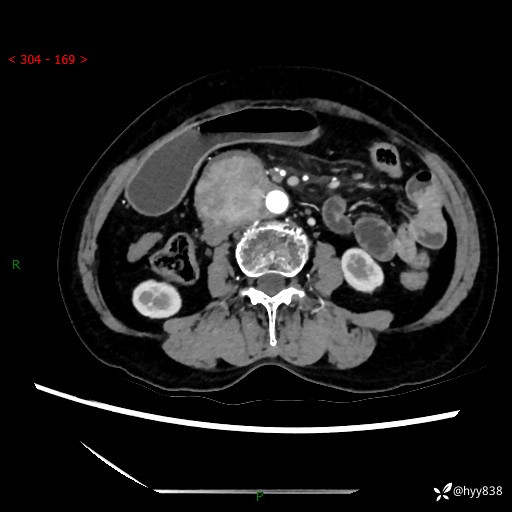

71岁/女,腹痛1月余。腹膜后肿物,间质瘤 VS 副节瘤 VS 平滑肌肉瘤---(有结果)

【患者信息】:71岁/女

【主诉】:腹痛1月余

【检查】:腹部CT增强扫描(外院CT平扫)